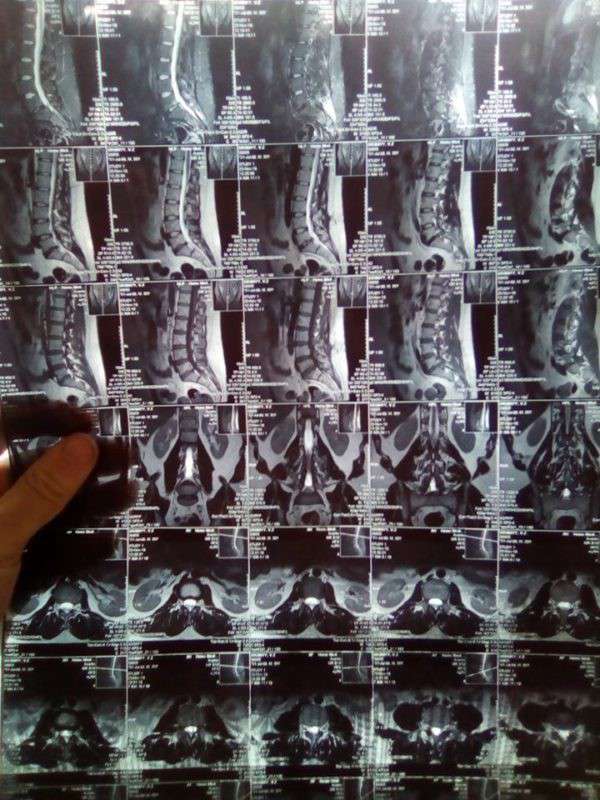

Минулоріч у чоловіка діагностували захворювання хребта. Спочатку було медикаментозне лікування, та згодом – операція. Після оперативного втручання легше не стало, – каже Василь, – навпаки, почала мучити жахлива біль. Вона настільки сильна, що ні сидіти, ні стояти, ні лежати молодий батько не може, і жодні знеболюючі препарати не допомагають.

За словами чоловіка, зараз він перебуває на лікуванні у Більче-Золотому. Та, як каже Василь, тут розводять руками, бо потрібна ще одна операція. Коштів звісно немає. Адже всі заощадження, які мала родина, вони вже витратили на попередню операцію з видалення міжхребцевої грижі та лікування впродовж року. Консультувалися з чернівецькими лікарями. Там чоловіка готові прийняти та прооперувати. Приблизна сума коштів, яку необхідно зібрати, 60 тисяч гривень, це не враховуючи післяопераційну реабілітацію, – розповідає Василь.